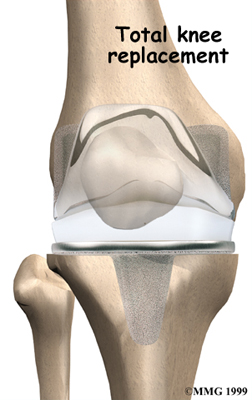

Artificial Knee Replacement

An artificial knee replacement is the ultimate solution for advanced knee OA.

Surgeons prefer not to put a new knee joint in patients younger than 60. This is because younger patients are generally more active and might put too much stress on the joint, causing it to loosen or even crack. A revision surgery to replace a damaged prosthesis is harder to do, has more possible complications, and is usually less successful than a first-time joint replacement surgery.

Related Document: FYZICAL Phoenix-Desert Ridge's Guide to Artificial Joint Replacement of the Knee